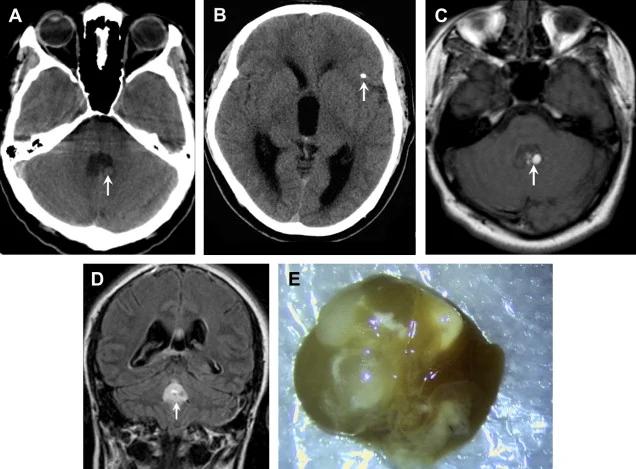

Ăn tiết canh, sán làm tổ trong não

Nếu chẳng may mắc sán não, chi phí điều trị lên đến hàng trăm triệu đồng. Nếu điều trị muộn, khả năng tử vong rất lớn hoặc có thể để lại di chứng sau này.